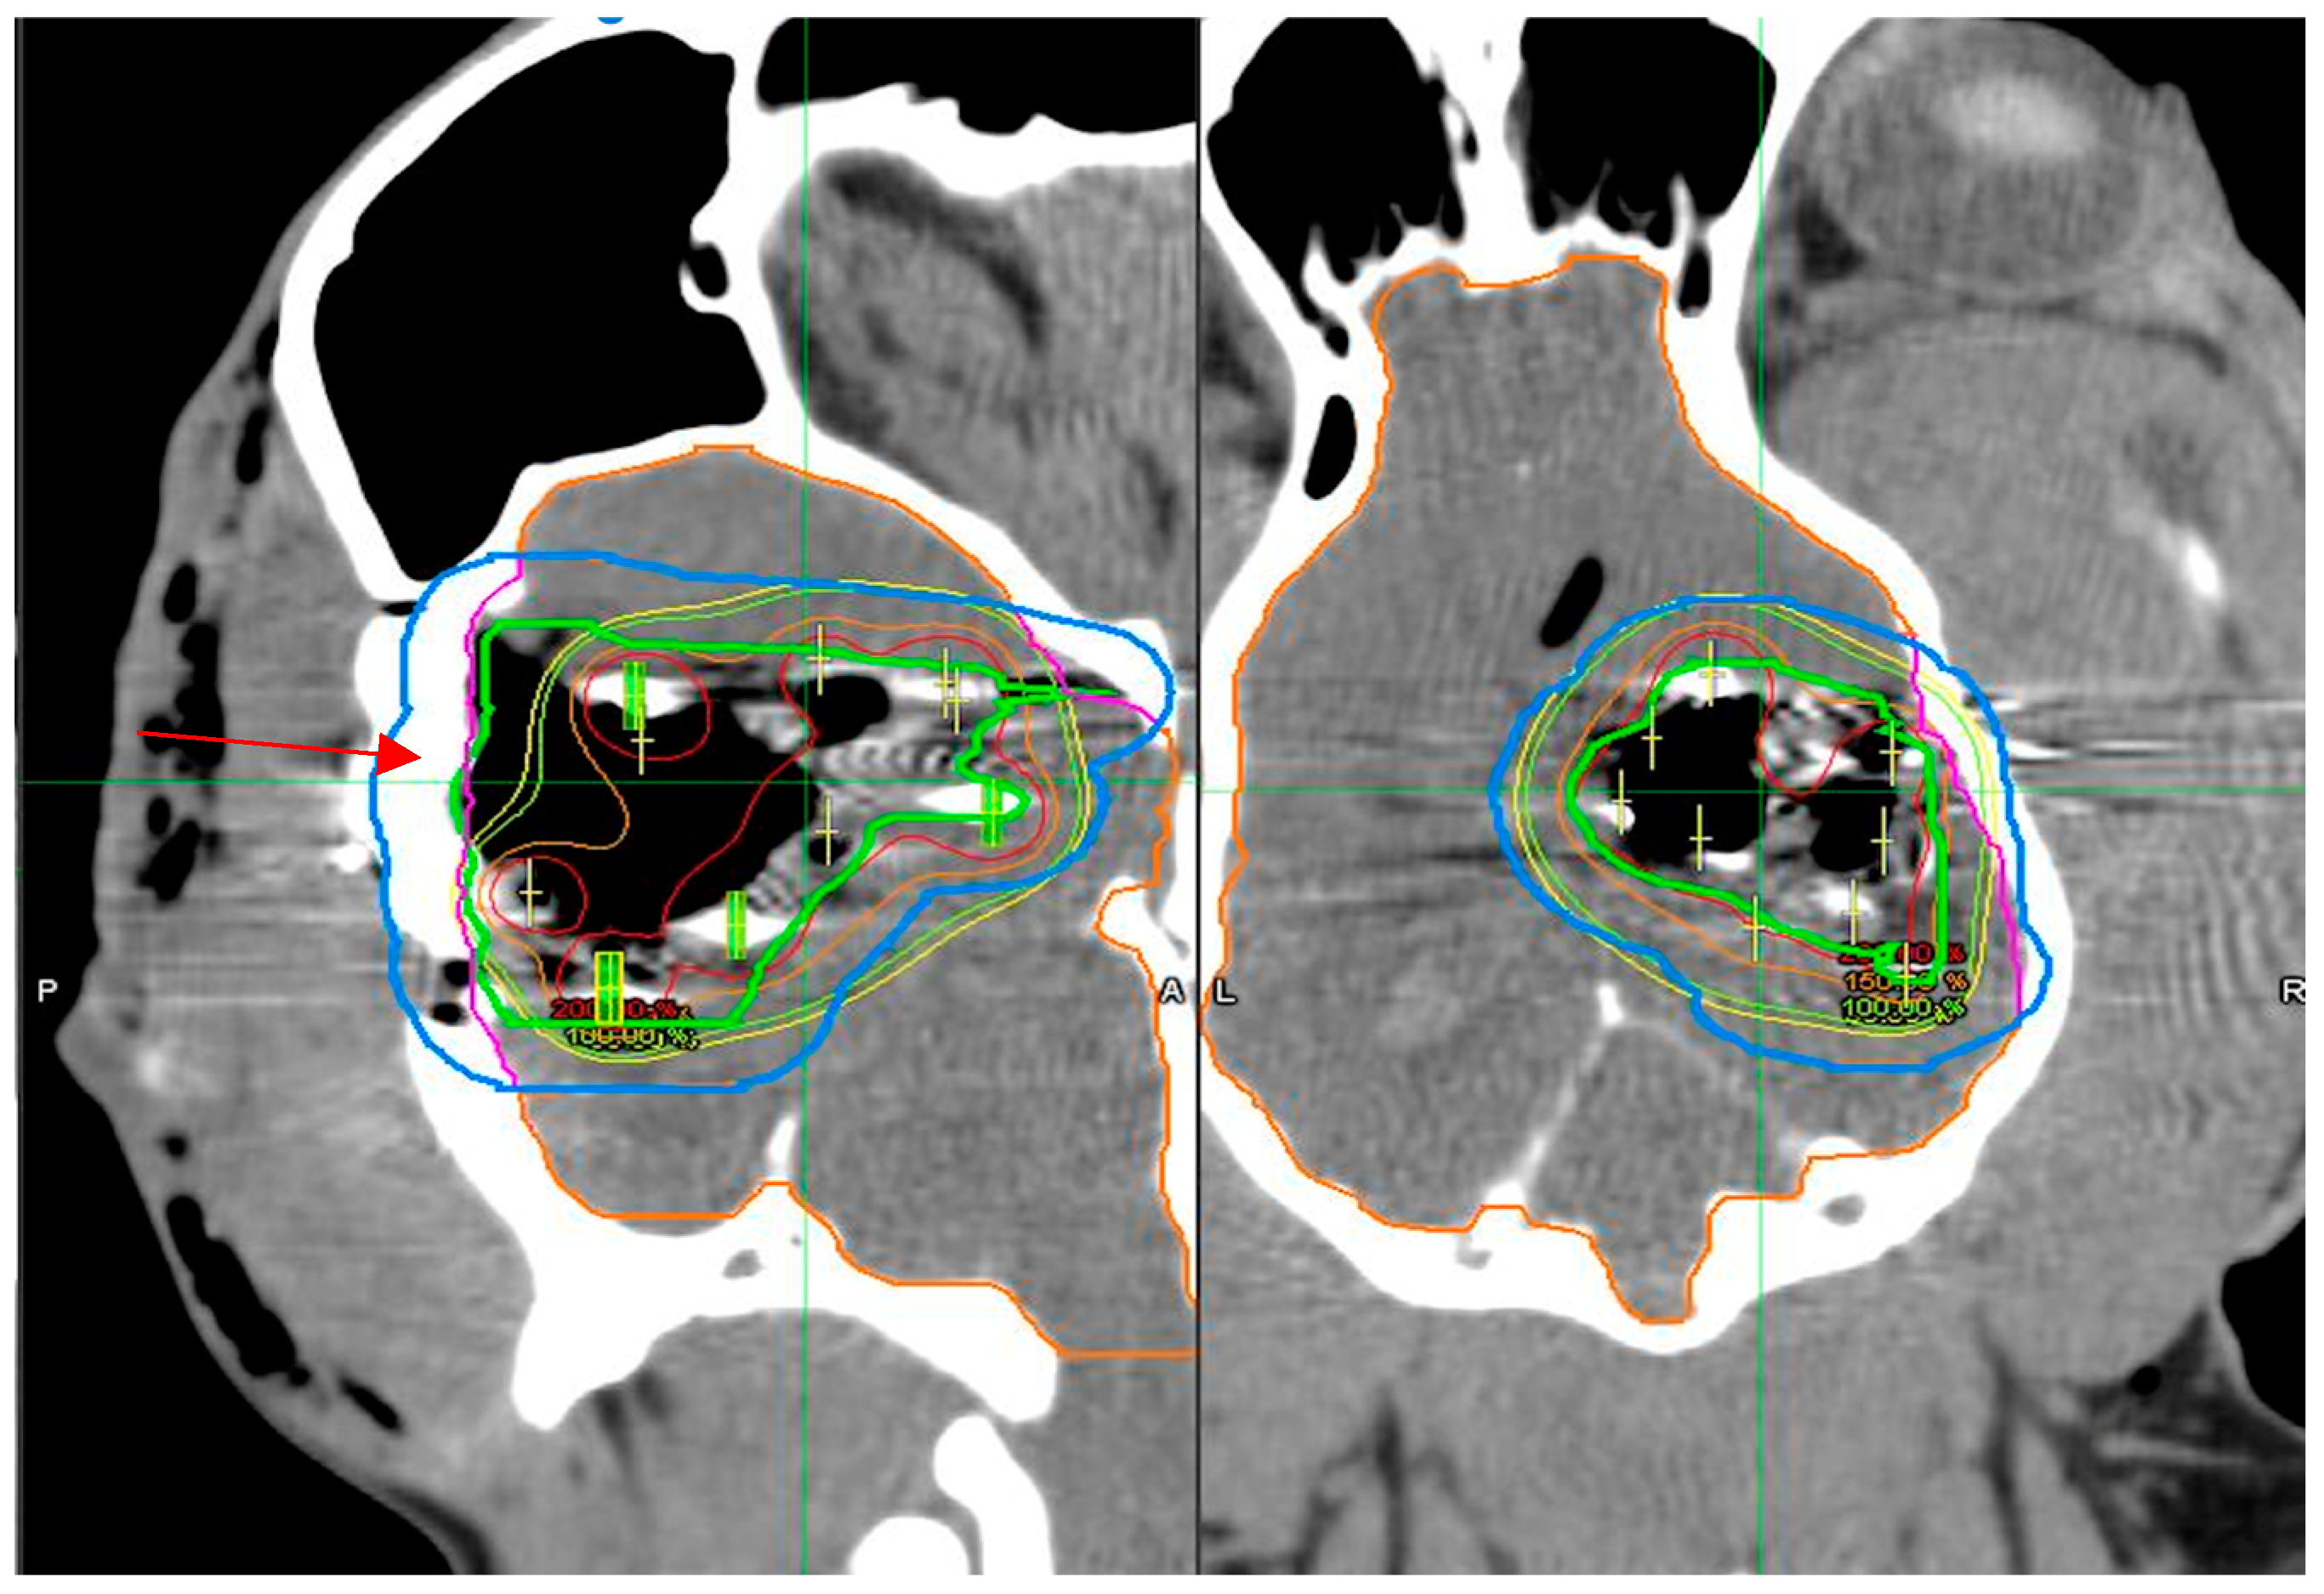

3.3. Dosimetry Verification